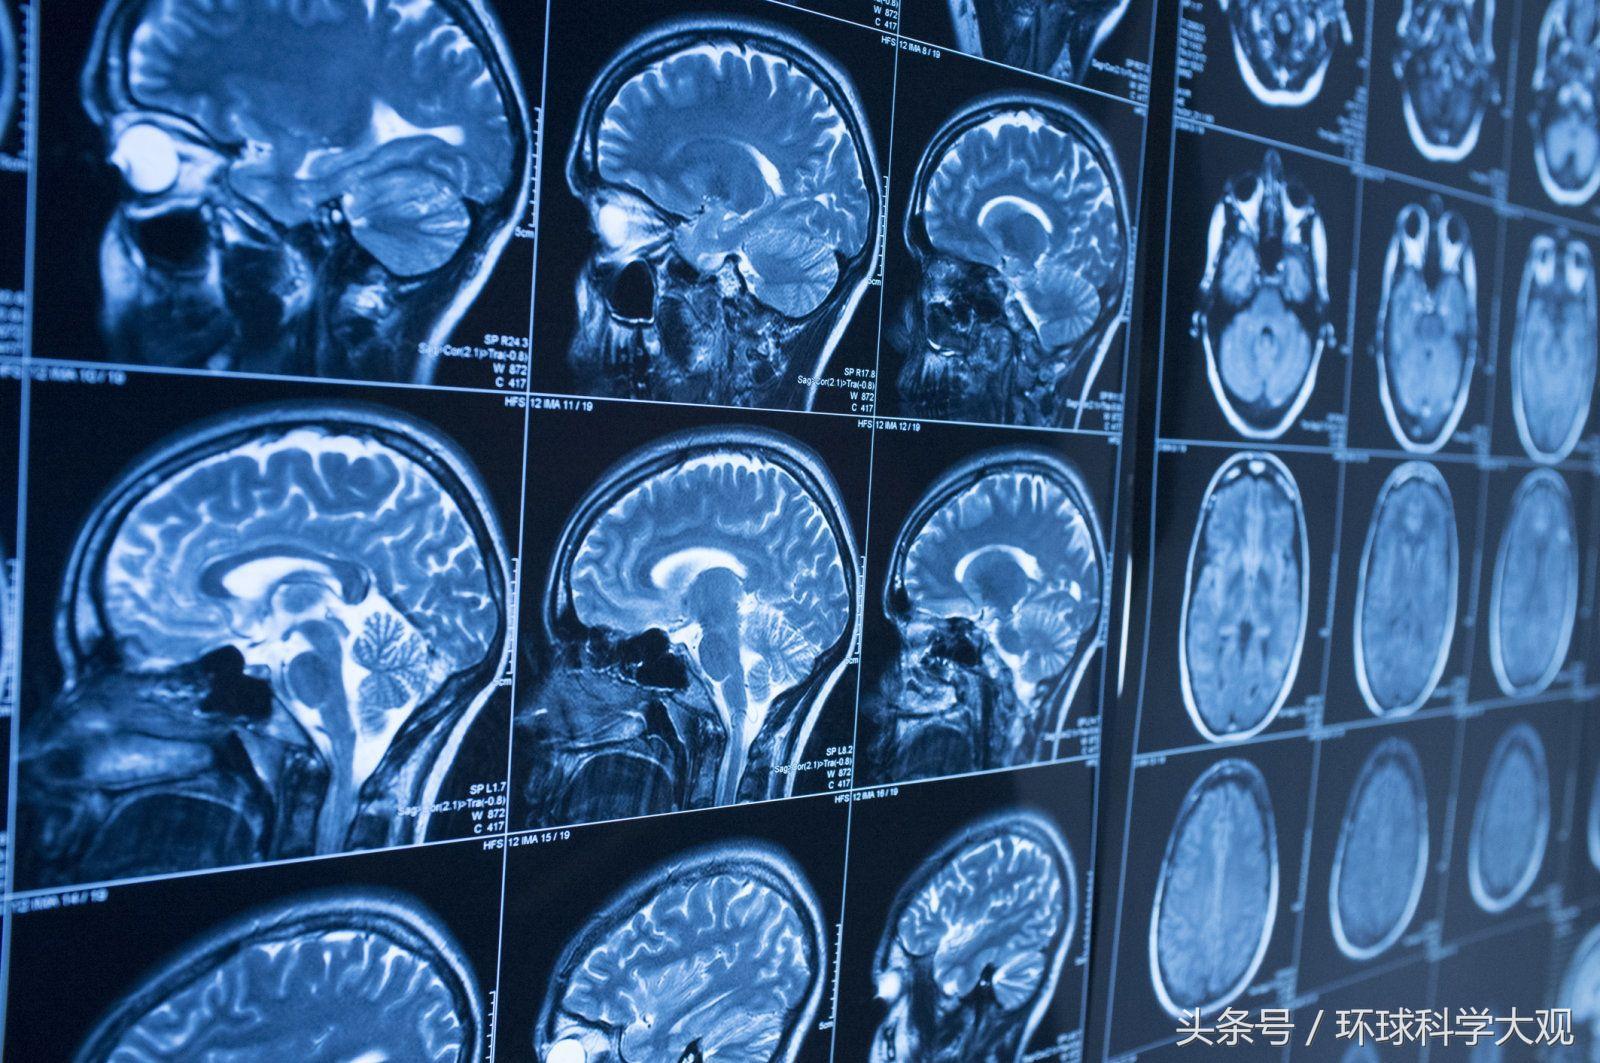

阿尔茨海默氏病(AD)俗称“老年痴呆症”,是一种发展缓慢的不可逆性大脑萎缩症,以记忆障碍、失语、失认、失用甚至人格和行为发生改变等全面性痴呆表现为特征,目前来说是无法治愈的。不过,近期来自美国俄亥俄州的一名华人科学家取得了一系列重要突破,治愈老年痴呆症或不再遥远!

在阿尔茨海默氏病形成初期,脑部β-淀粉样肽的异常堆积是一个显著的特征,从而在大脑中形成淀粉样斑块,扰乱神经突触的功能。而β-分泌酶(BACE1)正有助于产生这种导致患病的β-淀粉样肽。也就是说,只要将看似“多余”的BACE1从脑部移除,就可以避免β-淀粉样肽的堆积,从而达到治疗阿尔茨海默氏病的目的。